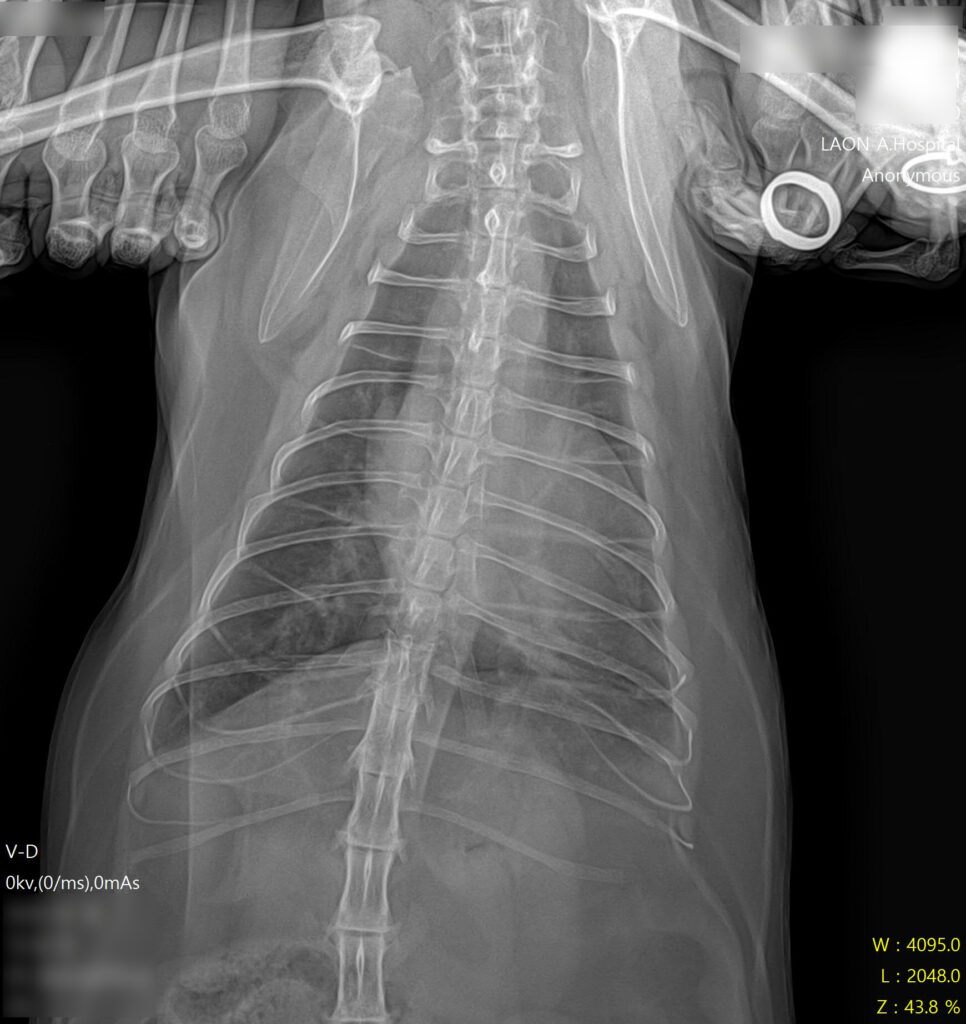

* 폐야가 하얗게 변한 폐수종 소견과 비대해진 심장 확인

- 방사선 검사: 흉부 방사선 촬영 결과, 폐 전반에 걸친 폐부종(pulmonary edema) 소견이 확인되었습니다. 또한 심장의 실루엣이 전형적인 ‘Valentine Shape(발렌타인 하트 모양)’으로 관찰되었는데, 이는 HCM(비대성 심근병증)에서 나타나는 특징적인 방사선 소견입니다.

* 폐수종 개선 및 깨끗해진 폐야 확인